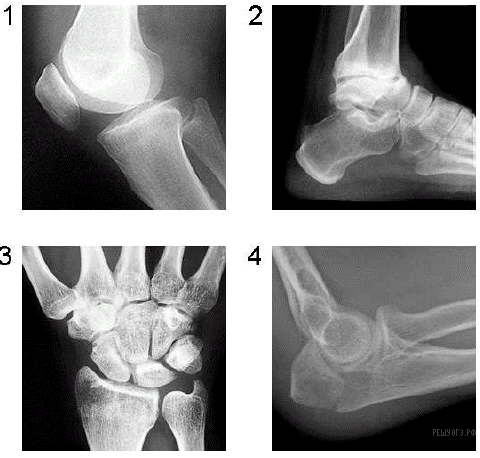

Какой цифрой на рентгенограмме отмечен локтевой сустав?

Ответ: